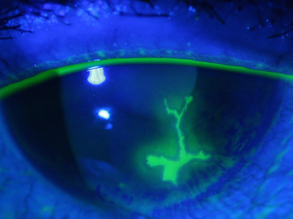

New Eye Cell